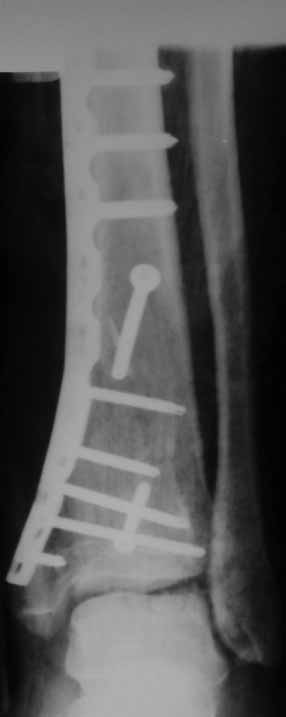

Отчет по "пилону":)))

Извиняюсь пропал - оперировал "пилон". В форуме не хотел обсуждать финансовые возможности пациента. Потянул комбинированную пластину. Опыт общение с пластиной "крест" есть - не очень понравилось - слишком много места занимает, даже с учетом обрезаний лишнего. Сделал доступ огибающий медиальную лодыжку спереди. В переднем крае оказался достаточно крупный отломок - удалось зафиксировать винтом. Дефекта кости не оказалось.

Остеосинтез практически подобного перелома представлен на сайте АО - там забугорные коллеги через передне-медиальный доступ сделали репозицию, передний край "собрали" на простейшей 1/3-трубчатой пластине, а все крупные отломки - с помощью медиальной мыщелковой пластины. Думаю, и то, и то есть в клинике?

Какой таран? в одном сегменте повреждается одно или другое. Крайне редко обе части. Анатомическая репозиция безукоризненна,но для чего межфрагментарный винт при использовании LCP это очевидное нарушение методики. А по поводу Мальтийского креста, то это оличный незаменимый, в ряде случаев, фиксатор, но не для этого перелома, абсолютно!С Уваением! Сергей.